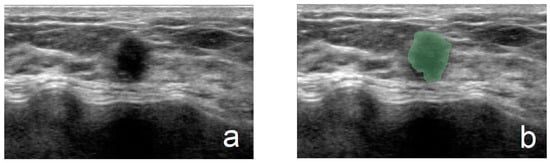

Another junior physician delineated the ROIs for all lesions without prior knowledge of the nodules’ pathological results. ROI delineation was performed using 3D Slicer software (version 5.6.1). All ultrasound images were standardized. During the delineation process, the physician used tools such as zooming, dragging, drawing, and tracing to precisely outline the margins of the lesions. For lesions with unclear margins, the delineations were reviewed and corrected by a senior physician. Figure 1 illustrates the ROI segmentation for benign and malignant breast nodules in ultrasound images. The completed ROI masks were saved in nii.gz format, and the standardized ultrasound images were saved in nii format, preparing them for subsequent ultrasound feature extraction in the Python language environment.

Figure 1.

(a,b) From a 45-year-old patient (fibroadenoma): (a) grayscale image and (b) ROI of a benign breast nodule. (c,d) From a 59-year-old patient (invasive ductal carcinoma): (c) grayscale image and (d) ROI of a malignant breast nodule.